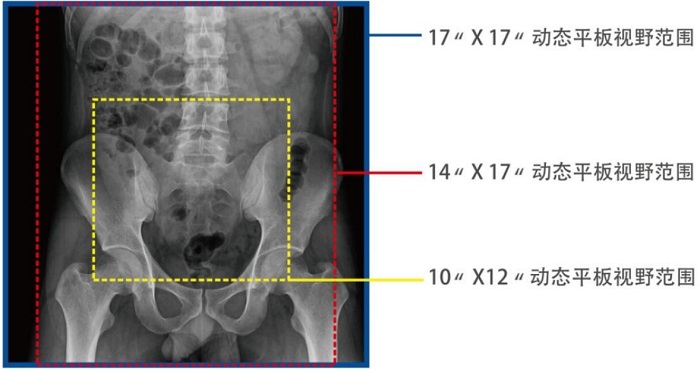

動(dòng)態(tài)DRF在肛腸科檢查中優(yōu)勢明顯。首先,17×17英寸大幅面成像,對于食道、胃、腸、結(jié)腸等大范圍成像部位,可一次曝光完成,極大減少了患者的輻射劑量和檢查時(shí)間,且空間分辨率高,與傳統(tǒng)胃腸機(jī)相比,圖像質(zhì)量大幅提升。